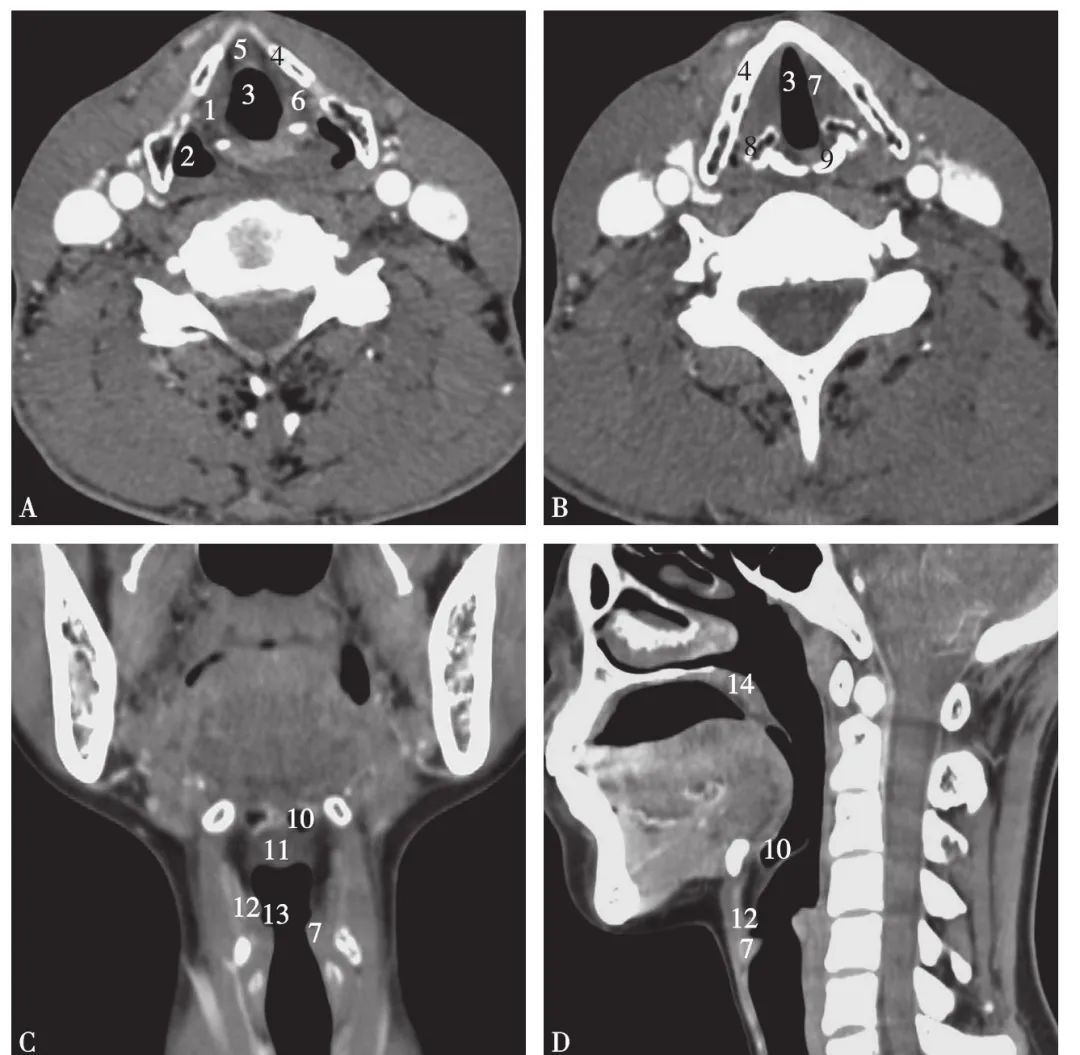

喉部解剖及喉癌影像表现

图片尺寸796x1150